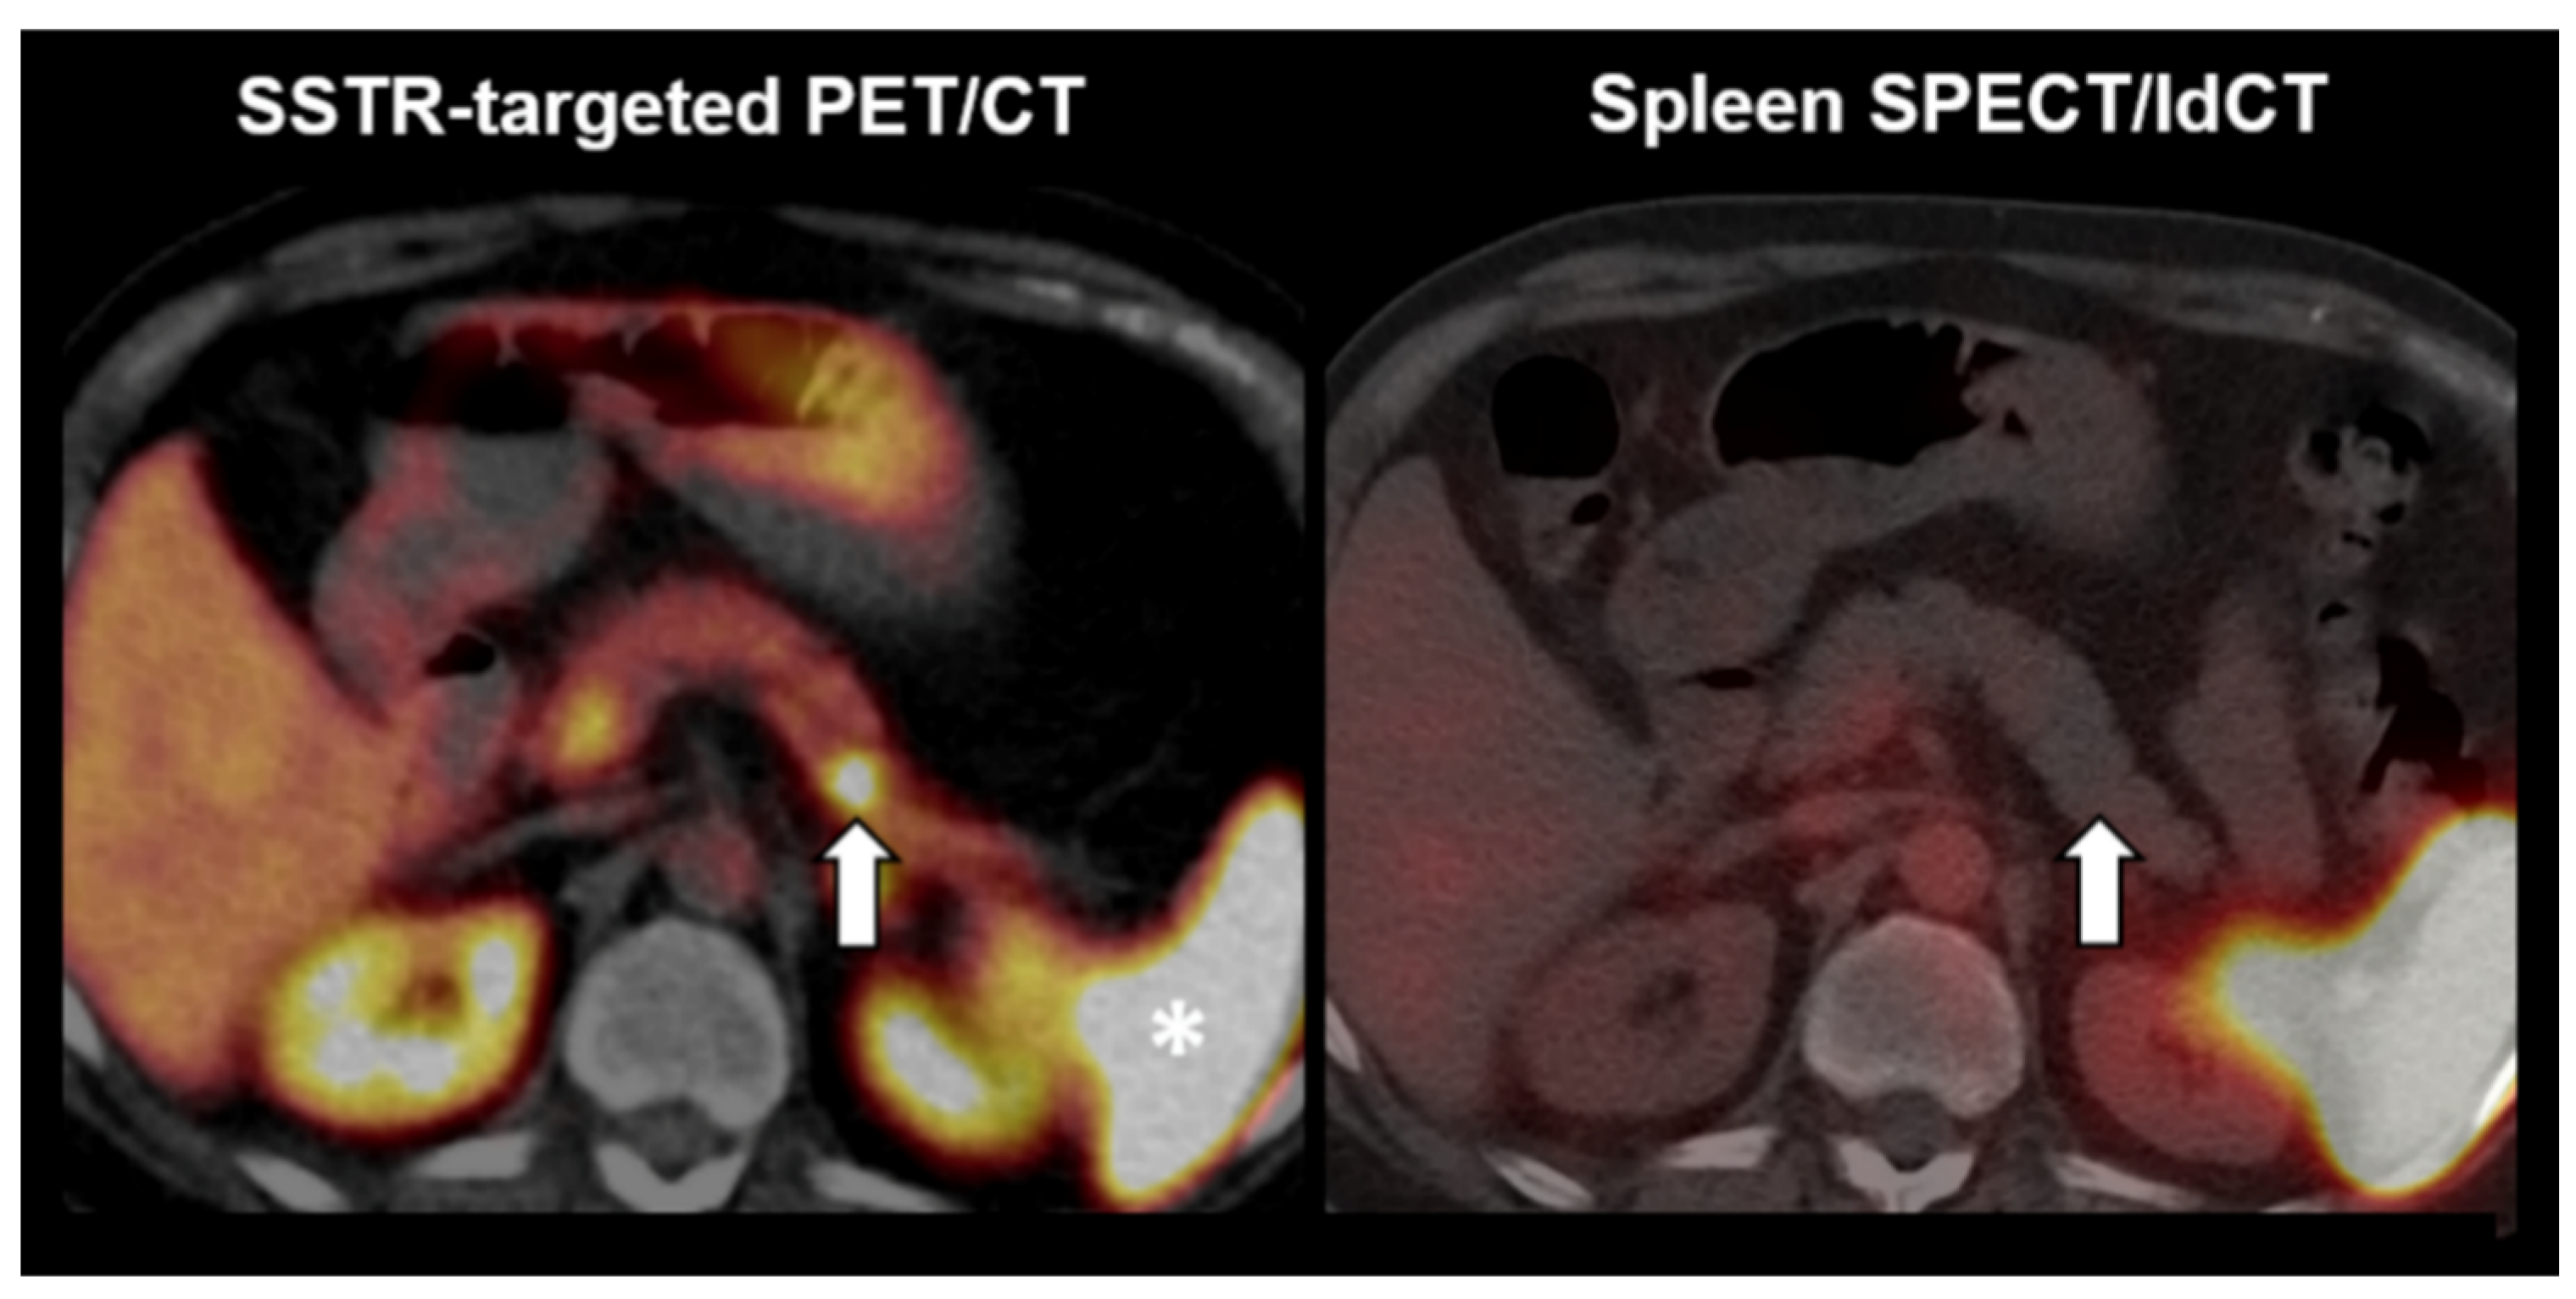

Figure 5 illustrates the case of a lesion rated as non-splenic tissue. A 67-year-old woman with an incidental lesion in the pancreatic tail presented for somatostatin receptor (SSTR)-targeted PET/CT (left). A strong focal tracer uptake in PET/CT suggested a neuroendocrine pancreatic neoplasm (see left arrow). The latter, however, cannot be differentiated from an intrapancreatic splenule in PET/CT, since both entities display a comparably high SSTR-ligand uptake despite their diametrically opposed prognosis (note the high physiologic SSTR-ligand uptake in the spleen; see asterisk). Yet, the pancreatic lesion was not visible in endoscopy and, therefore, not accessible to ultrasound-guided fine needle aspiration cytology and biopsy. Hence, the interdisciplinary tumor board review recommended 99mTc-labelled denatured red blood cells scintigraphy to rule out a splenule (right; SPECT fused to low dose CT). Here, no increased uptake is noted in the pancreatic lesion (see right arrow). Taking into account the scintigraphy results, a laparoscopic distal pancreatectomy was performed, and histopathology ultimately confirmed the diagnosis of a neuroendocrine tumor of the pancreas. Using the quantitative reading in selective spleen scintigraphy, the lesion would have been correctly classified (lower lesional uptake ratio than the cutoff, i.e., 0.49 < 0.75).

Figure 5.

Example of a negative reading in spleen scintigraphy. (Left) Somatostatin receptor (SSTR)-targeted PET/CT. (Right) 99mTc-labelled denatured red blood cells SPECT fused to low dose CT. Arrows = the suspected lesion. Asterisk = physiologic SSTR radioligand uptake in the spleen.